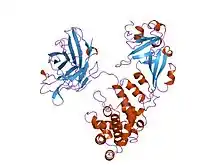

Cartoon representation of the diphtheria toxin protein | |||||||

The crystal structure of the diphtheria toxin homodimer has been determined to 2.5 Ångstrom resolution. The structure reveals a Y-shaped molecule consisting of three domains. Fragment A contains the catalytic C domain, and fragment B consists of the T and R domains:[5]

- The amino-terminal catalytic domain, known as the C domain, has an unusual beta+alpha fold.[6] The C domain blocks protein synthesis by transfer of ADP-ribose from NAD to a diphthamide residue of eukaryotic elongation factor 2 (eEF-2).[7][8]

- A central translocation domain, known as the T domain or TM domain, has a multi-helical globin-like fold with two additional helices at the amino terminus but no counterpart to the first globin helix. This domain is thought to unfold in the membrane.[9] A pH-induced conformational change in the T domain triggers insertion into the endosomal membrane and facilitates the transfer of the C domain into the cytoplasm.[7][8]

- A carboxy-terminal receptor-binding domain, known as the R domain, has a beta-sandwich fold consisting of nine strands in two sheets with Greek-key topology; it is a subclass of immunoglobulin-like fold.[6] The R domain binds to a cell surface receptor, permitting the toxin to enter the cell by receptor-mediated endocytosis.[7][8]